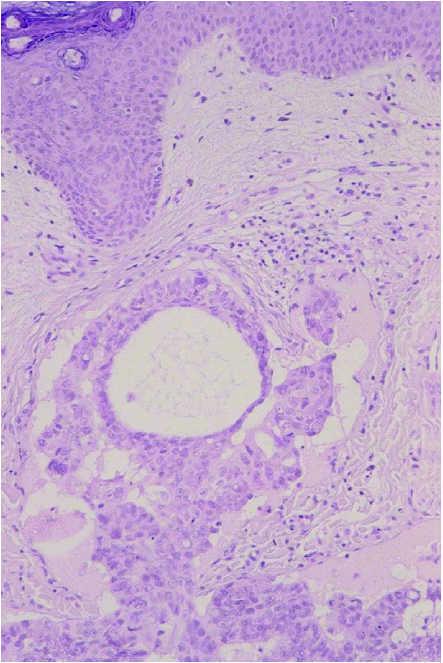

Un varón de 62 años, sin antecedentes personales de interés, ingresó en el hospital para estudio de una anemia microcítica de 4 meses de evolución y diarrea. Desde hacía 2 meses el paciente presentaba unas lesiones cutáneas eritematosas, asintomáticas, localizadas en la fosa iliaca, ingle y tercio superior del muslo izquierdo, previamente diagnosticadas como herpes zóster por su médico de familia y tratadas con famciclovir oral sin mejoría. En la exploración física se observaban múltiples pápulas y vesículas sobre una base eritematosa, infiltradas, localizadas en la fosa iliaca, pubis, ingle, y tercio superior del muslo izquierdo, distribuidas siguiendo el dermatoma L1-L2 (fig. 1). Se acompañaban de un discreto linfedema del miembro inferior izquierdo. Se practicó biopsia cutánea cuyo estudio histopatológico mostró una epidermis normal, sin evidencia de infección viral y una dermis cuyos vasos linfáticos aparecían permeados por grupos de células de aspecto tumoral (fig. 2). Estas células eran grandes, pleomórficas, algunas de citoplasma claro con el núcleo desplazado hacia la periferia, remedando un «anillo de sello» (fig. 3). Estos hallazgos eran compatibles con una invasión linfática diseminada por células de un adenocarcinoma pobremente diferenciado. Ante estos datos y por la clínica que tenía el paciente se solicitó una colonoscopia, con la que se apreció una formación de características malignas en recto, tendente a estenosar. El estudio histopatológico de la lesión fue de adenocarcinoma de recto. Se completó estudio con gammagrafía ósea, en el que no se hallaron metástasis óseas y tomografía computarizada (TC) toracoabdominal en el que se observó, aparte de la masa tumoral, una adenopatía en área inguinal izquierda y adenopatías retroperitoneales altas de características metastásicas. El paciente fue intervenido quirúrgicamente y remitido al Servicio de Oncología para tratamiento con quimioterapia y radioterapia.

Fig. 2.--Dermis con vasos linfáticos permeados por grupos de células de aspecto tumoral. (Hematoxilina-eosina, ×40.)

Fig. 3.--Células grandes, pleomórficas, algunas de citoplasma claro con el núcleo desplazado hacia la periferia remedando un «anillo de sello». (Hematoxilina-eosina, ×100.)